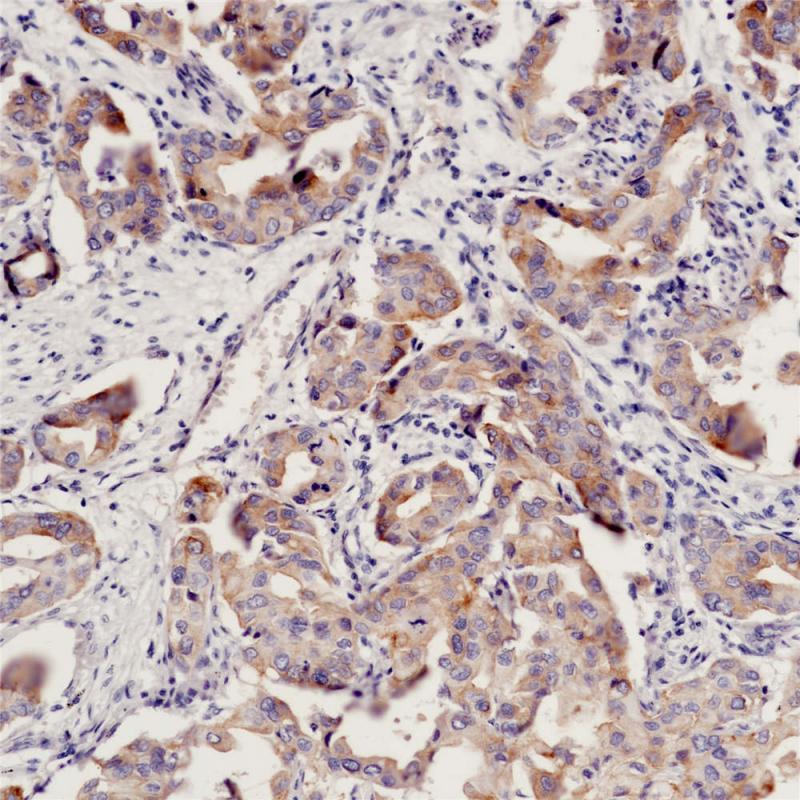

EGFR(L858R) 重组兔单克隆抗体

EFGR L858R为EGFR的其中一种基因突变类型,其突变主要发生在18/19/20/21外显子,21外显子编码的第858个氨基酸因为mRNA的第2553位密码子T置换为G使得编码氨基酸由亮氨酸(英文缩写为L)变成了精氨酸(英文缩写为R),上述突变引起EGFR下游通路的激活,导致肿瘤的发生。

阳性对照

肺癌

亚细胞定位

细胞膜/细胞质